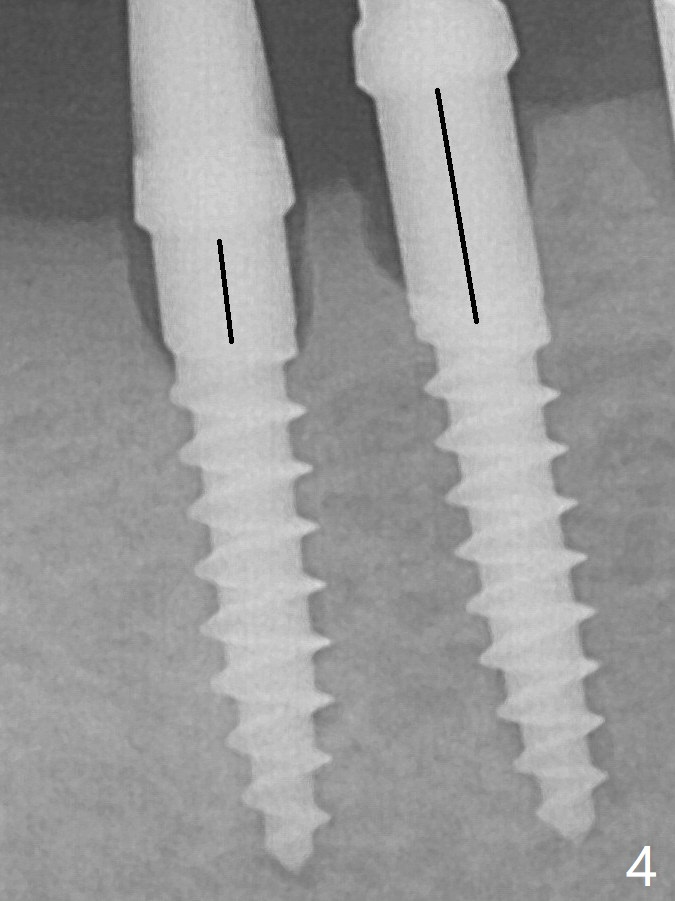

Since the mesial implant is high in occlusion, the cuff of the distal implant is changed to be 2 mm (Fig.4 (shorter black line)). The crestal bone around the implants resorbs 5 months postop (Fig.7).

Two of 2.5 mm 1-Piece Implants Last Next